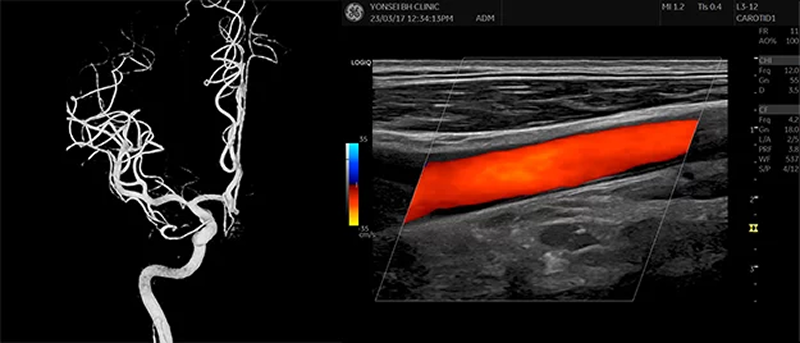

연세BH의원은 상담 및 문진 후 경동맥 초음파로 1차 평가를 진행하며,

필요 시 뇌혈관 조영술(TFCA)을 시행해 협착·동맥류·혈류 이상을 정밀 확인합니다.

연세BH의원은 경동맥 초음파와 4만 5천건 이상의 혈관 조영술 경험을 바탕으로,

아주 미세한 위험요인까지 사전에 발견하여 뇌경색과 뇌출혈의 위험을 조기에 차단하고